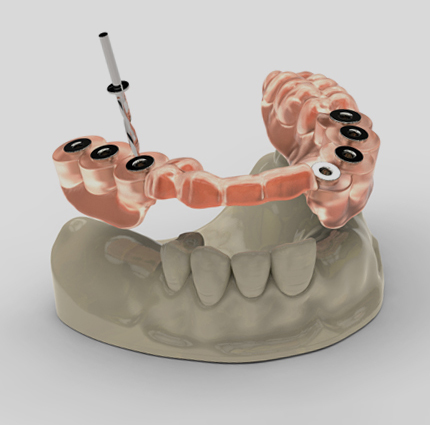

- 신경치료

- '발치'는 최후의 선택! 고난도 재신경치료로 자연치아를 살리다

- 신경치료

- 신경치료

- '발치'는 최후의 선택! 고난도 재신경치료로 자연치아를 살리다

- 충치치료

- 조금이라도 살릴 수 있다면

끝까지 포기하지 않고 치료 방법을 고민합니다. - 치과보존과 전문의

- 성 소 래 원장 /자연치아살리기, 고난도 신경치료, 심미레진